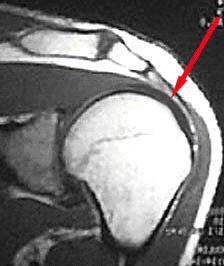

In addition to the types of symptoms experienced by the patient and the physical exam findings, imaging studies are often very useful in diagnosing rotator cuff injuries. Plain radiographs do not show soft tissues particularly well, but indirect evidence seen on plain films often indicates rotator cuff injury. These may include spurring on the undersurface of the acromion or AC joint, cystic changes in the greater tuberosity, calcifications within the rotator cuff, and possibly a high-riding humeral head. The most definitive imaging technique to help with the diagnosis of rotator cuff injuries is magnetic resonance imaging (MRI). A well-done MRI with a high field magnet is typically excellent at determining the presence or absence of tendinosis, partial tearing or full-thickness tearing, and also provides specific information as to the size and location of the injury. It also provides information as to chronicity and reparability of the tear by revealing the extent of atrophy or fatty infiltration of the various rotator cuff muscles.

MRI – normal Rotator Cuff

MRI – Rotator Cuff tear